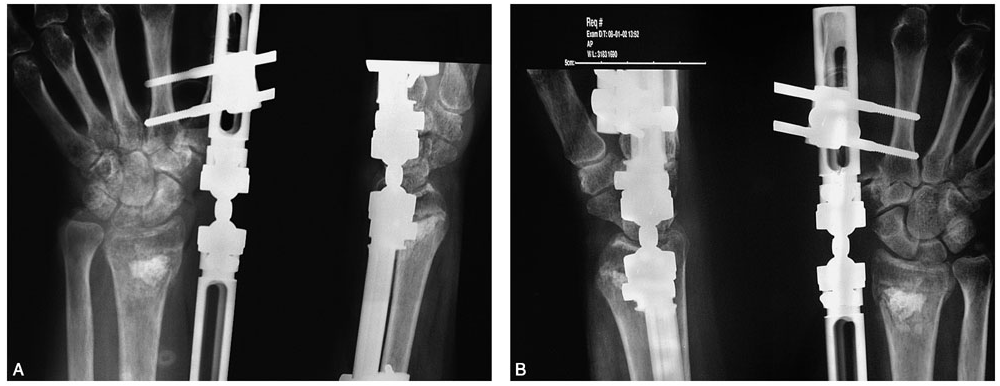

术前拍腕关节正、侧位X线片,腕关节冠状位、矢状位和水平位CT(图2-2)。此患者骨缺损和无法闭合复位的骨片均在背侧,宜采用背侧入路,复位,植骨,固定。取患肢前臂远端桡背侧纵切口(图2-3),从伸拇长肌腱和桡侧伸腕长、短肌之间进入,注意保护血管神经和肌腱,显露清理折端骨缺损区域和背侧移位的骨片(图2-4),复位,植骨,外固定架超关节固定(图2-5、图2-6)。术中透视骨折复位固定满意(图2-7),术后拍X线片证实(图2-8)。此手术的优点在于避免了局部存在内固定物的刺激,避免二期切开取出固定物所致的再次损伤。

图2-7 术中透视示骨折复位、固定、植骨满意

图2-8 术后X线片示骨折复位、固定、植骨满意